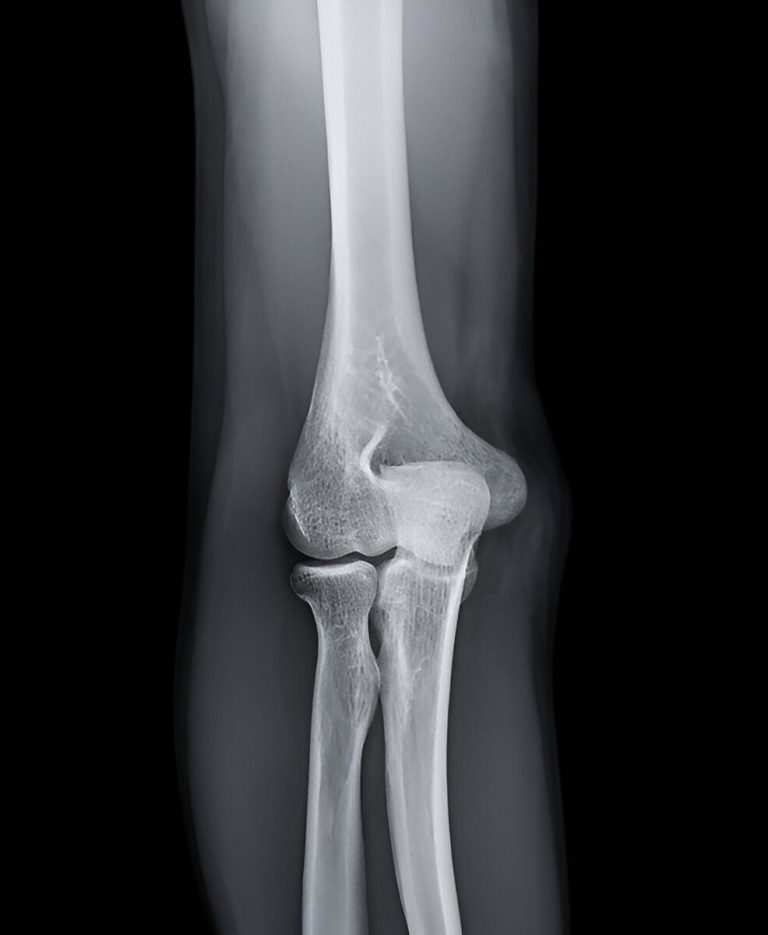

What Is an Olecranon Fracture?

An olecranon fracture is a break in the bony tip of the elbow, part of the ulna—one of the two forearm bones. The olecranon forms the pointed end of the elbow and serves as the attachment site for the triceps tendon, allowing extension of the elbow.

This injury can vary from a simple, nondisplaced crack to a complex break with displacement, joint involvement, or multiple fragments. Because the olecranon is exposed and lacks protective soft tissue, it is particularly vulnerable to trauma.

• X-rays to assess the location, number of fragments, and displacement of the fracture